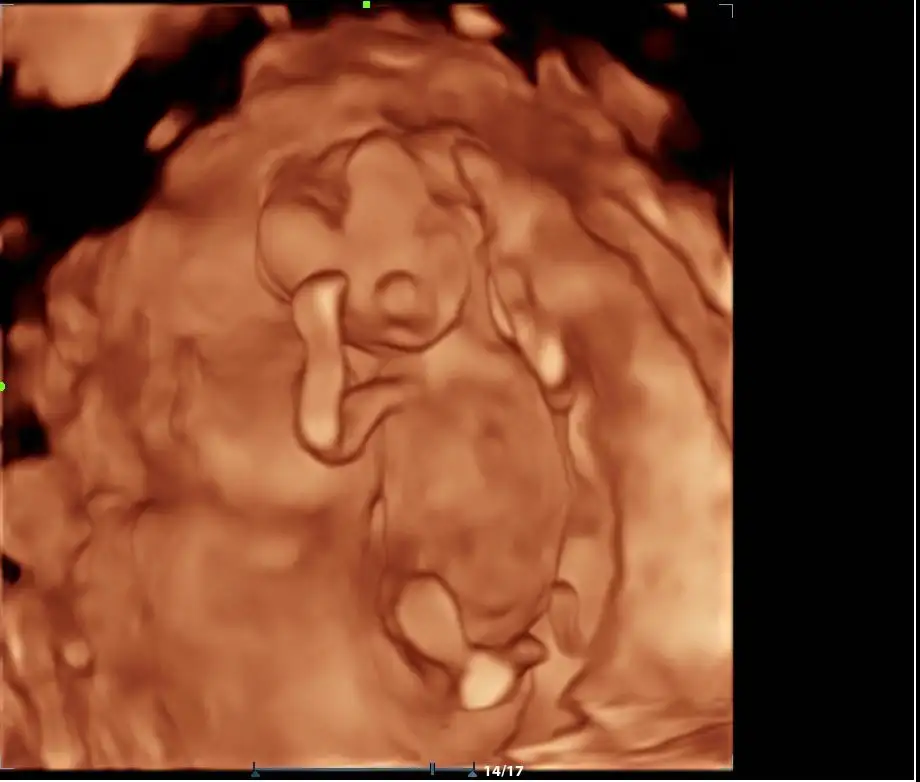

Pregnancy Confirmation

5-12 week

This early ultrasound is performed to confirm pregnancy, visualize the gestational sac, yolk, and fetal pole.

- Early Peek (8–14 weeks) – See baby’s movements and heartbeat